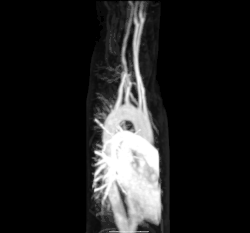

Кровь, лишенная кислорода, из верхней и нижней полых вен поступает в правое предсердие сердца и течет через трехстворчатый клапан (правый атриовентрикулярный клапан) в правый желудочек, из которого затем перекачивается через легочный полулунный клапан в лёгочную артерию в легкие. В легких происходит газообмен, при котором из крови выделяется CO2, а кислород поглощается. Лёгочная вена возвращает обогащенную кислородом кровь в левое предсердие[10].

Малый круг кровообращения — это часть сердечно-сосудистой системы, в которой обедненная кислородом кровь откачивается от сердца через лёгочную артерию в легкие и возвращается, насыщенная кислородом, к сердцу через лёгочную вену.

Кровь, лишенная кислорода, из верхней и нижней полых вен поступает в правое предсердие и течет через трехстворчатый клапан (правый атриовентрикулярный клапан) в правый желудочек, из которого затем перекачивается через лёгочный полулунный клапан в лёгочную артерию. В легких происходит газообмен, при котором из крови выделяется CO2, а кислород поглощается. Лёгочная вена возвращает обогащенную кислородом кровь в левое предсердие[10].

Большой круг кровообращения — это часть сердечно-сосудистой системы, которая переносит насыщенную кислородом кровь от сердца через аорту из левого желудочка, где кровь ранее депонировалась из малого круга кровообращения, в остальную часть тела и возвращает обедненную кислородом кровь обратно в сердце[10].

Насыщенная кислородом кровь поступает в большой круг кровообращения при выходе из левого желудочка через аортальный клапан[15]. Первой частью большого круга кровообращения является аорта, массивная и толстостенная артерия. Аорта изгибается и разветвляется, снабжая кровью верхнюю часть тела, пройдя через аортальное отверстие диафрагмы на уровне десятого грудного позвонка, входит в брюшную полость[16]. Затем ветви аорты спускаются в живот, таз, промежность и нижние конечности[17] .